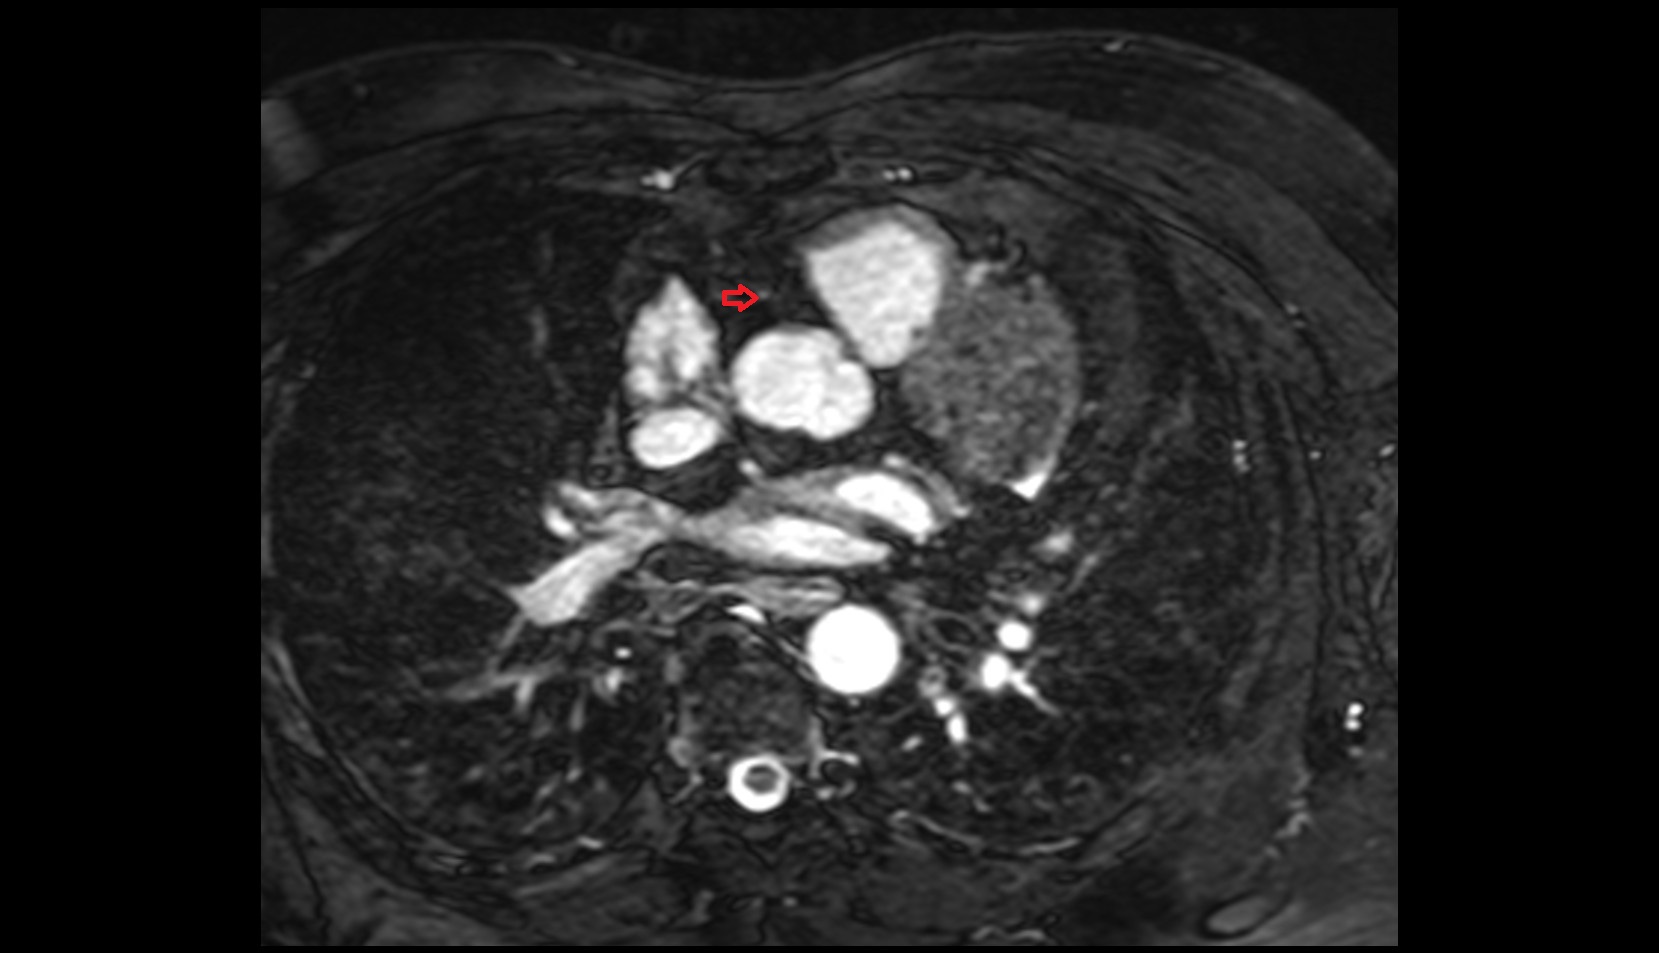

- Middle cerebral artery horizontal segment (M1)

- Middle cerebral artery insular segment (M2)

- Middle cerebral artery opercular segment (M3)

- Middle cerebral artery cortical segment (M4)